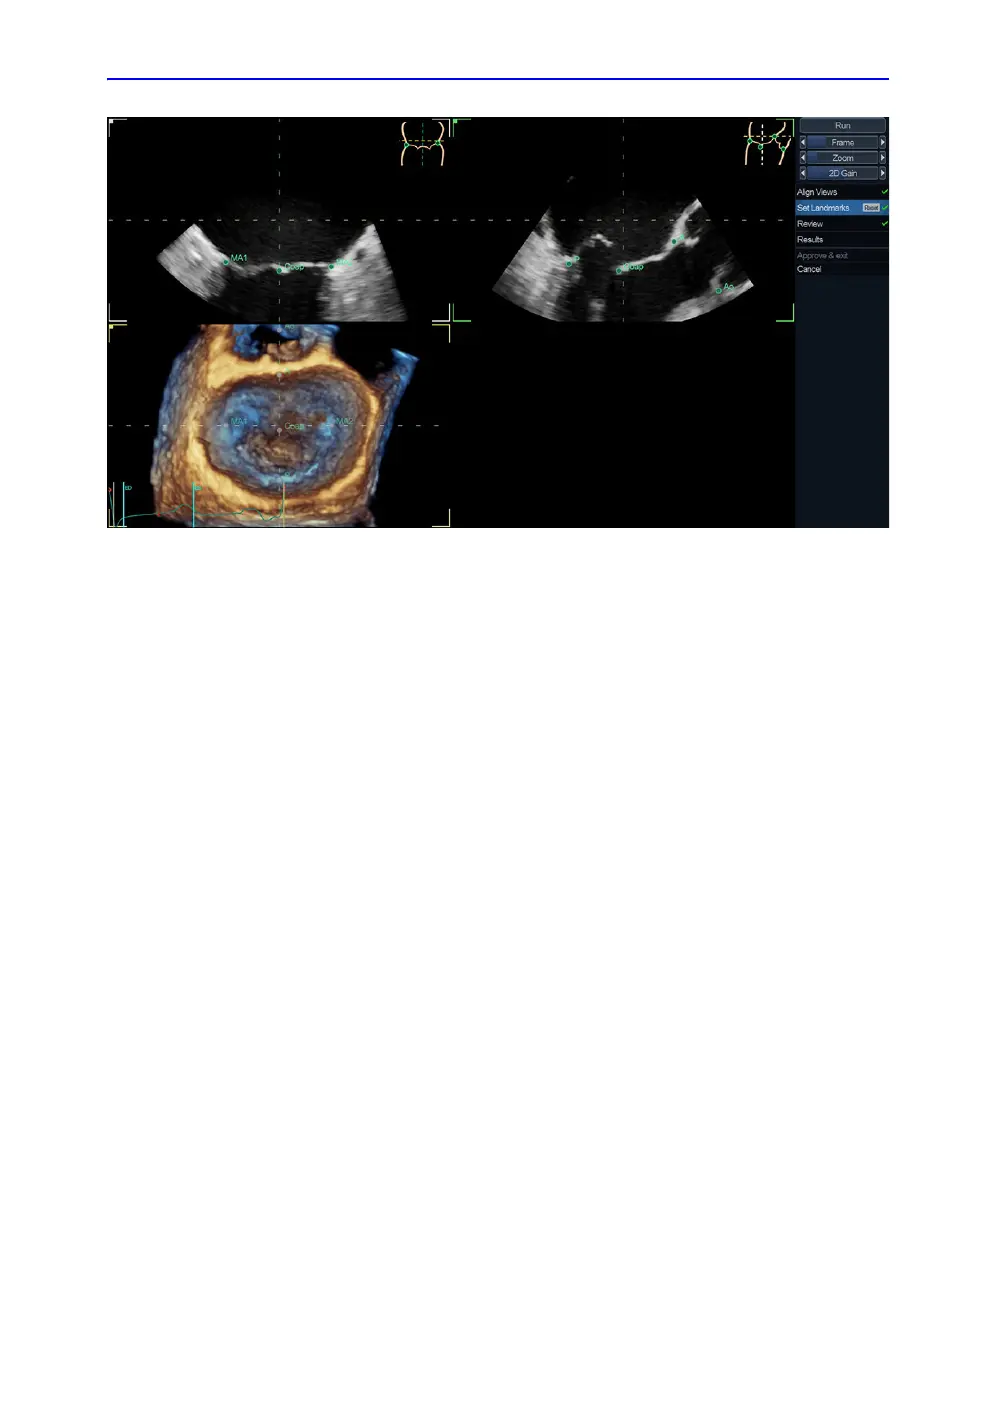

4D Auto MVQ

Figure 8-37. Set Landmark stage